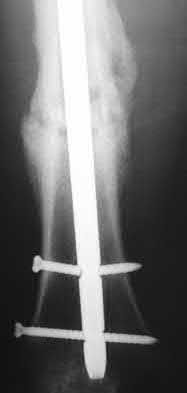

1. # A 32-year-old male sustains the injury shown in Figure A and undergoes treatment as shown in Figure B. Following placement of this implant, what is the best technique to confirm it is not too proud proximally?

The safe zone for tibial nail placement as seen on radiographs is just medial to the lateral tibial spine on the anteroposterior radiograph and immediately adjacent and anterior to the articular surface as visualized on the lateral radiograph.

Tornetta et al specifically located the safe zone for nail entry in a study using fresh frozen cadaver knees. The authors found that the safe zone for nail placement is located 9.1+/-5 millimeters lateral to the midline of the plateau and three millimeters lateral to the center of the tibial tubercle. The width of the safe zone averaged 22.9 millimeters and was as narrow as 12.6 millimeters.

The starting point of the of the nail can be best viewed on the lateral knee radiograph, an example of which is shown in Illustration A. Illustration B shows the "sweet spot" for nail insertion as defined by Tornetta.